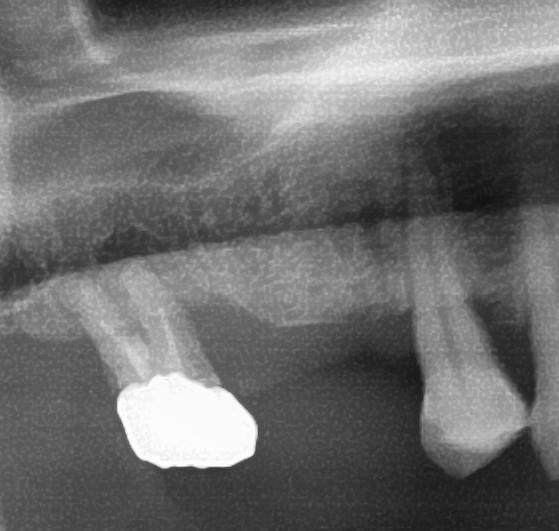

今回の患者様はインプラント植立を希望され、右上5番目・6番目の合計2本の植立が決まりました。